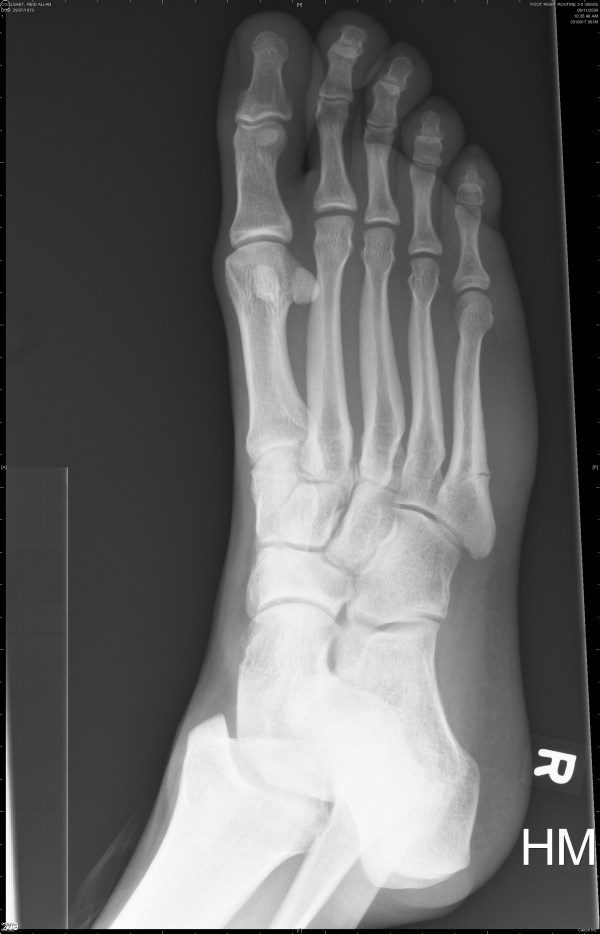

The first two are from November 6th and the last two are from November 22nd.

Nov. 22